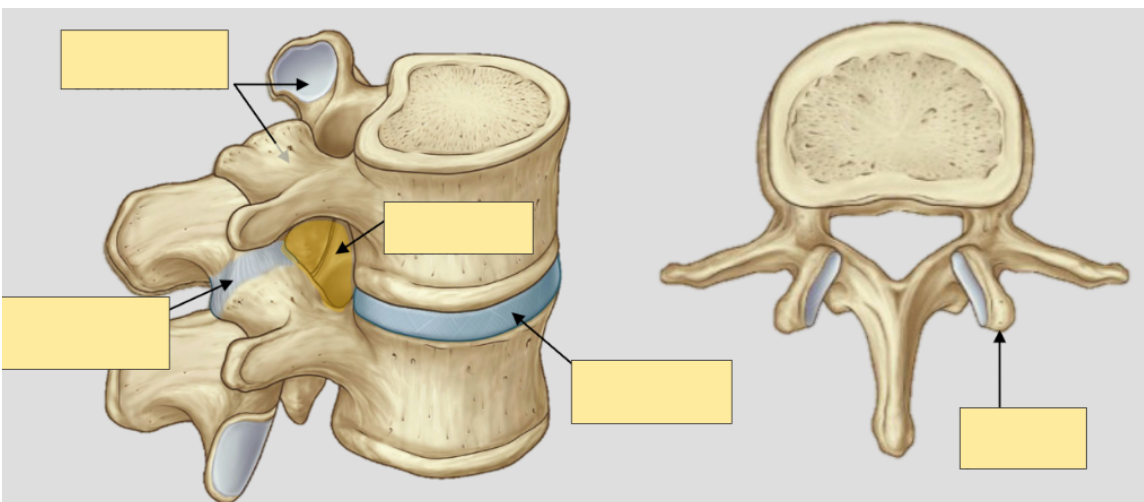

What are intervertebral discs?

What is the function of intervertebral discs?

What is the structure of intervertebral disc?

What is the intervertebral disc a remnant of?

and label

• fibrocartilage between vertebrae which provide string attachment between vertebral bodies

• shock absorbers

• outer anulus fibrosus (consisting of type 1 and 2 collagen fibres) and inner nucleus pulposus

• remnant of notocord